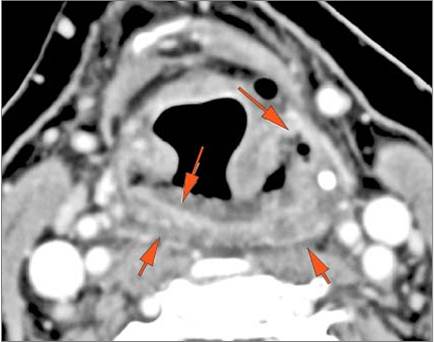

There is edema within the adjacent deep neck, retropharyngeal and/or prevertebral spaces [Yes/No]

There is abscess within the adjacent deep neck, retropharyngeal and/or prevertebral spaces. [Yes/No]